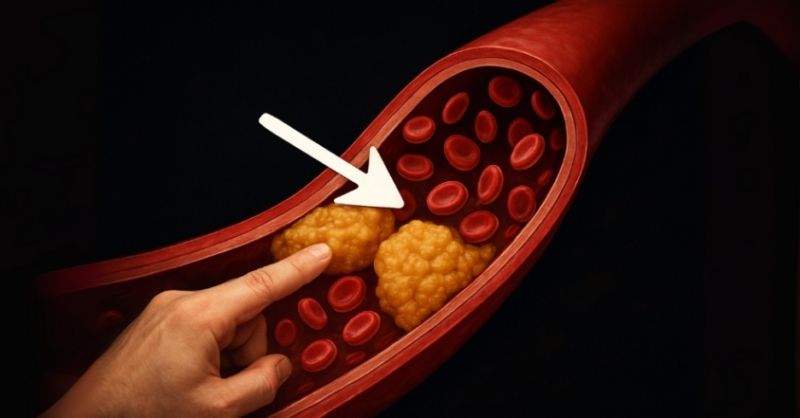

What is thrombosis and what are its symptoms?

Thrombosis is a potentially serious condition in which a blood clot forms inside a blood vessel, obstructing the normal flow of blood. If left undiagnosed or untreated, it...

Eat this #1 meal to help unclog your arteries naturally

We’re often told what not to eat for heart health — sugar, fat, cholesterol. But what if the real solution lies in eating smarter, not just avoiding things?...